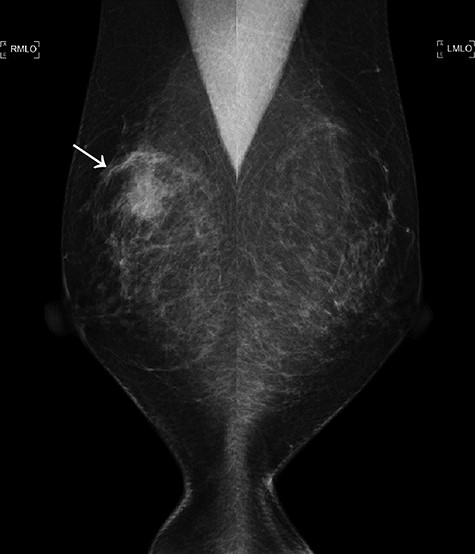

A 52-year-old woman with no medical history presented with an abnormality in her right breast that was detected on screening mammography. She has a strong family history of breast cancer, with her mother and twin sister being affected. Ultrasonography, mammography and computerized tomography displayed a 21 mm mass in her right breast (Figs 1 and 2A). A core-needle biopsy (CNB) demonstrated invasive carcinoma with features of matrix-producing carcinoma (Fig. 3). The clinical stage was cT2N0M0. Immunohistochemistry revealed that the tumor was negative for the estrogen receptor, progesterone receptor and human epidermal growth factor receptor 2 (HER2), with a Ki-67 score of 90%. Although BRCAnalysis® test was recommended after genetic counseling, she refused it because of its lack of insurance coverage in Japan.

The first mammogram. The mammogram displaying a highly dense micro-serrated mass in the right upper lateral region (arrowhead).